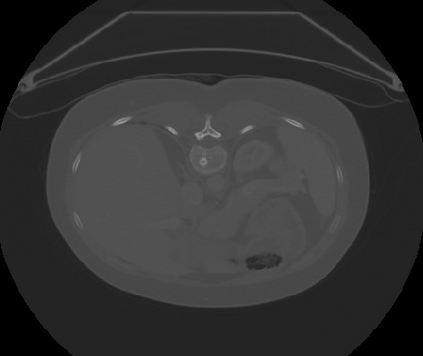

Transformers, the default model of choices in natural language processing, have drawn scant attention from the medical imaging community. Given the ability to exploit long-term dependencies, transformers are promising to help atypical convolutional neural networks (convnets) to overcome its inherent shortcomings of spatial inductive bias. However, most of recently proposed transformer-based segmentation approaches simply treated transformers as assisted modules to help encode global context into convolutional representations without investigating how to optimally combine self-attention (i.e., the core of transformers) with convolution. To address this issue, in this paper, we introduce nnFormer (i.e., Not-aNother transFormer), a powerful segmentation model with an interleaved architecture based on empirical combination of self-attention and convolution. In practice, nnFormer learns volumetric representations from 3D local volumes. Compared to the naive voxel-level self-attention implementation, such volume-based operations help to reduce the computational complexity by approximate 98% and 99.5% on Synapse and ACDC datasets, respectively. In comparison to prior-art network configurations, nnFormer achieves tremendous improvements over previous transformer-based methods on two commonly used datasets Synapse and ACDC. For instance, nnFormer outperforms Swin-UNet by over 7 percents on Synapse. Even when compared to nnUNet, currently the best performing fully-convolutional medical segmentation network, nnFormer still provides slightly better performance on Synapse and ACDC.